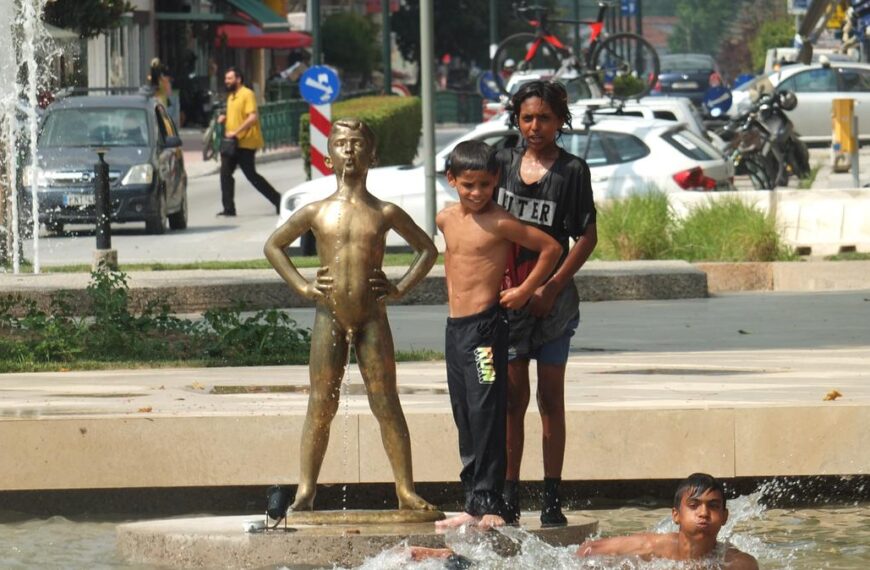

Η Πνευμονολογική Κλινική του Πανεπιστημιακού Νοσοκομείου Λάρισας και το Ακτινολογικό Εργαστήριο του Πανεπιστημιακού Νοσοκομείου σε συνεργασία με την Διοίκηση και το Υγειονομικό προσωπικό της δομής φιλοξενίας μεταναστών-προσφύγων στο Κουτσόχερο οργανώνει έλεγχο των φιλοξενούμενων στη δομή, για αποκλεισμό ενεργού πνευμονικής φυματίωσης.

Στους φιλοξενούμενους θα προηγηθεί δοκιμασία Mantoux και θα ακολουθήσει ακτινολογικός έλεγχος,

Αναμένεται τις επόμενες εβδομάδες να ελεγχθούν περισσότεροι από 300 φιλοξενούμενοι στην δομή.